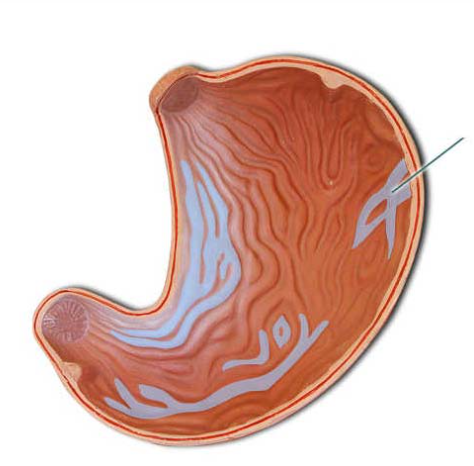

Identify the highlighted structures.

rugae